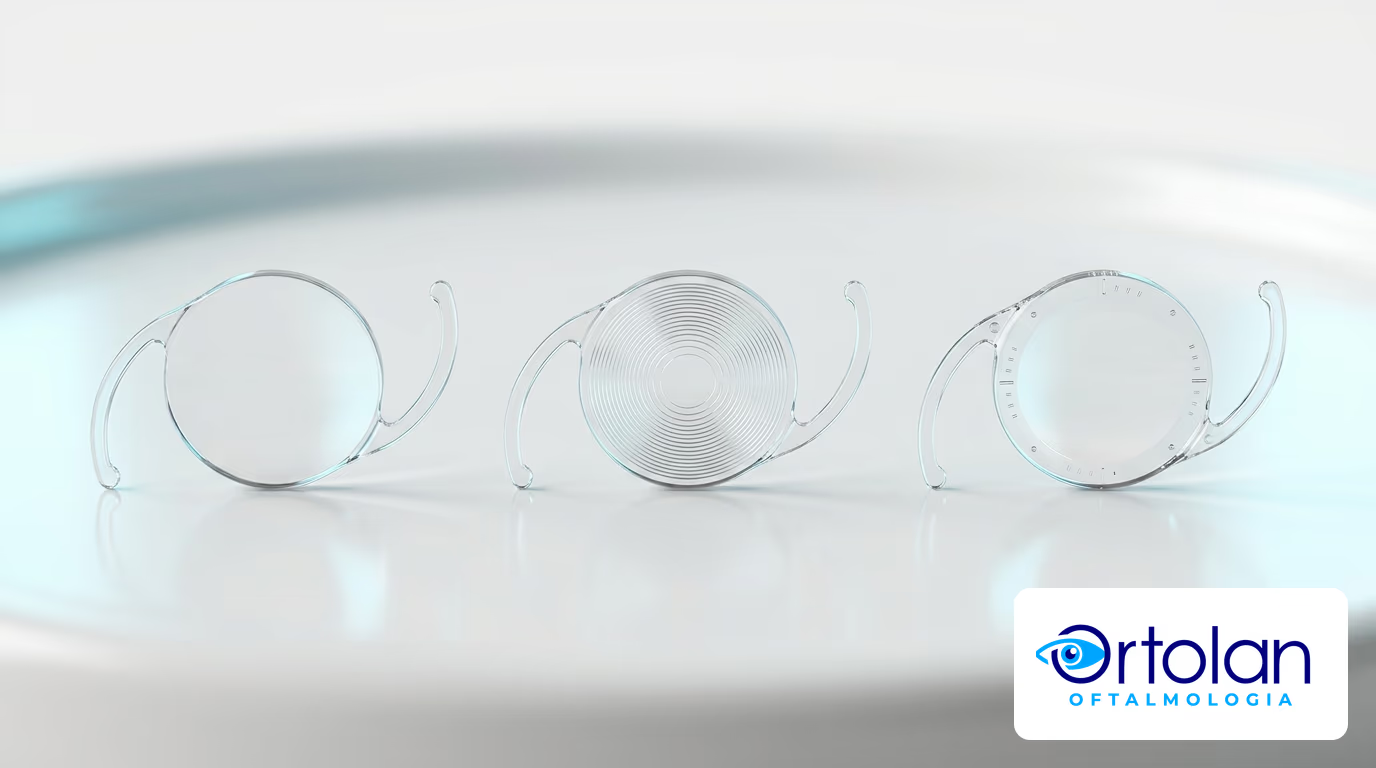

As lentes intraoculares modernas são dobráveis, o que permite incisões mínimas. A escolha depende do estilo de vida, das expectativas e dos exames pré-operatórios. Os principais tipos são:

- Lente monofocal: corrige a visão em uma única distância, geralmente longe. Pode ser esférica ou asférica, o que melhora a qualidade da imagem periférica. É a opção coberta pelos planos de saúde e pelo SUS.

- Lente multifocal: corrige longe, intermediário e perto, reduzindo a dependência de óculos. Existem variantes trifocais e de foco estendido.

- Lente tórica: corrige astigmatismo associado. Pode ser monofocal tórica ou multifocal tórica.